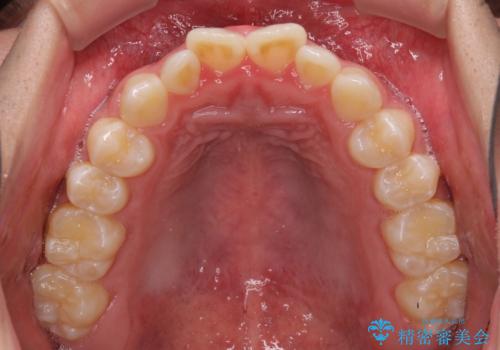

受け口傾向特有の狭い上顎歯列であったため、歯列の拡大を補助装置で行い、下顎歯列全体を後方に移動させることとしました。

奥歯の咬み合わせを改善させた後、上下左右の小臼歯(下顎は残存乳歯)を計4本抜歯し、ワイヤー装置にて口元の突出感を改善しながら咬み合わせを整えることとしました。

下顎の残存乳歯は小臼歯よりも大きいため、スペースを閉じるために長い期間を必要としますが、予想通りに長期間を要することとなりました。